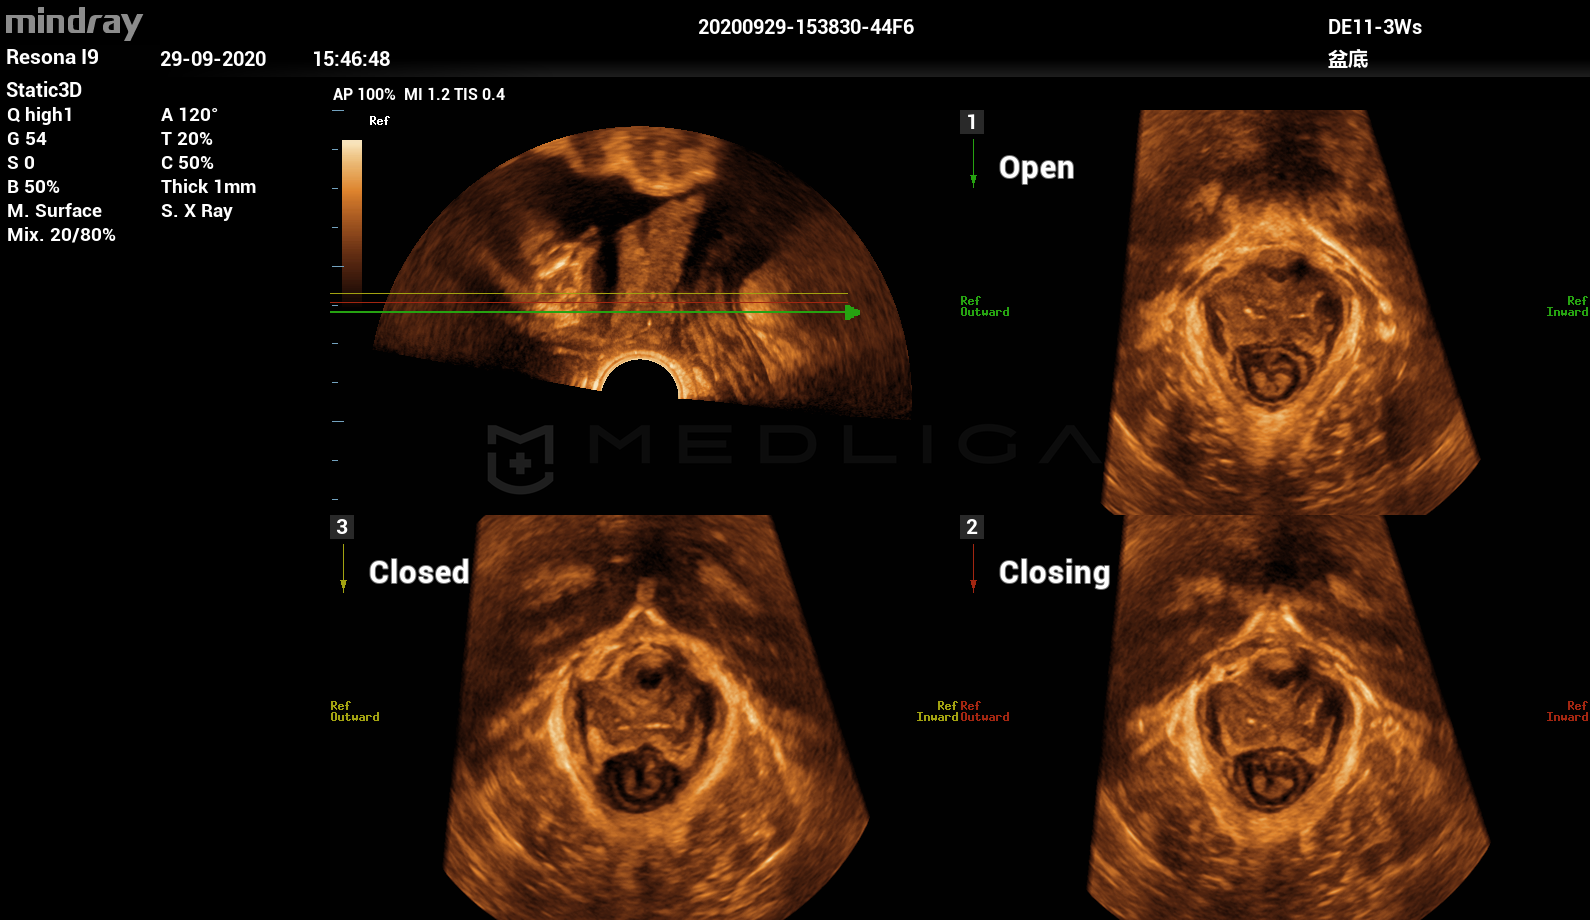

Программное обеспечение для автоматических измерений параметров и оценки функции мышц тазового дна.

Smart Pelvic - новое решение, позволяющее значительно упростить диагностическую процедуру и свести к минимуму время исследования функций мышц тазового дна. Благодаря чрезвычайно простому пользовательскому интерфейсу, программа генерирует стандартную систему координат и автоматически просчитывает все связанные измерения в течение нескольких секунд.